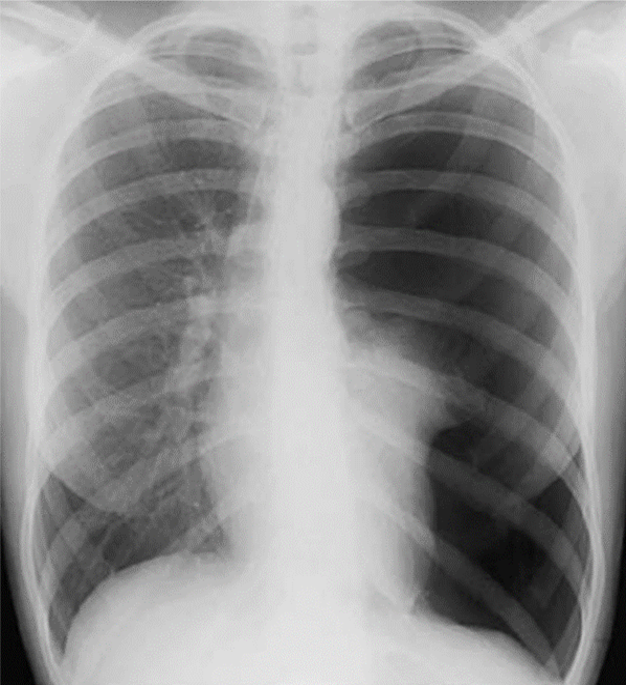

1-Tràn khí màng phổi (T) lượng nhiều gây xẹp phổi thụ động